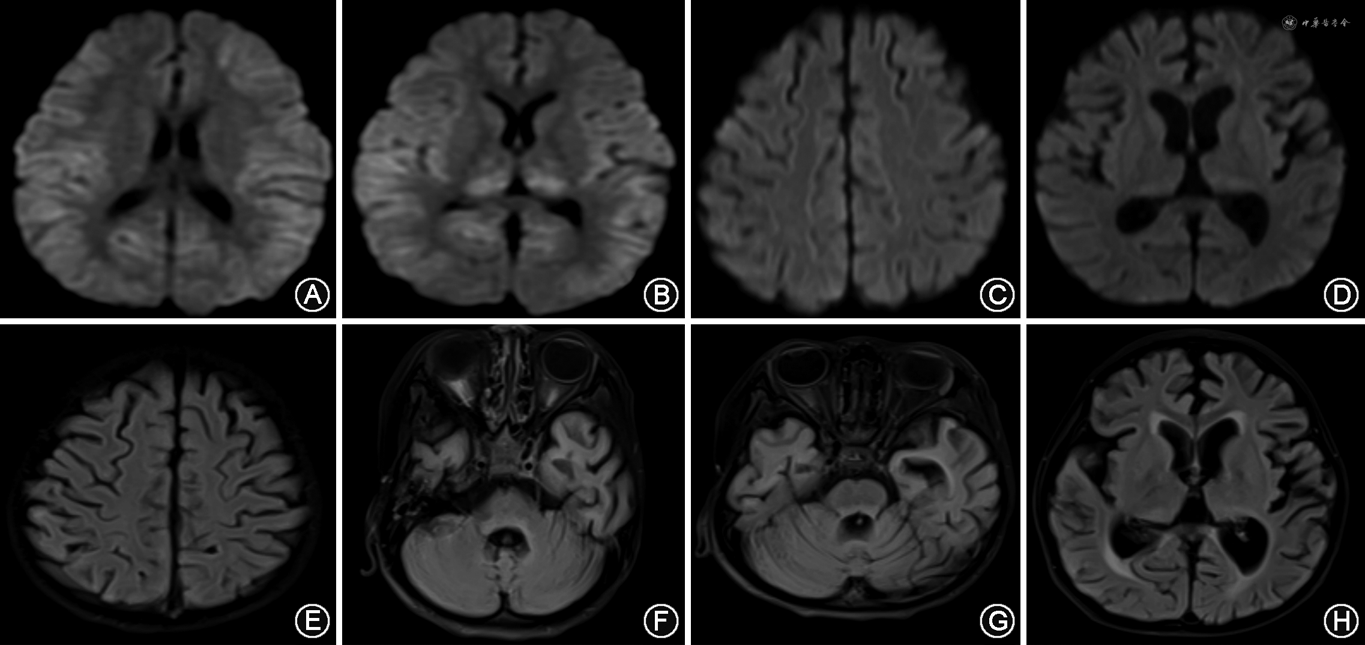

实验室及影像学检查:脑脊液常规、生化、涂片、培养及脑脊液宏基因组二代测序(metagenomic next-generation sequencing,mNGS)均正常,脑脊液乳酸2.87 mmol/L(正常值1.00~2.78 mmol/L),脑脊液白细胞介素6 17.66 pg/ml(正常值<5.30 pg/ml),血白细胞介素6 329.6 pg/ml;脑脊液及血液的自身免疫性脑炎相关抗体以及副肿瘤综合征抗体均阴性;血生化、血氨、血乳酸、铜蓝蛋白、同型半胱氨酸、丙酮酸、甲状腺功能均正常;血、尿遗传代谢未见异常;极长链脂肪酸水平正常;血毒物筛查未见异常。患儿视频脑电图动态改变见图1,头颅MRI动态改变见图2。

入院后2个月患儿无临床发作,脑电图提示弥漫性慢波活动、阵发性痫样波发放,最终抗发作药物调整为:拉考沙胺(10 mg· kg-1· d-1)、唑尼沙胺(8.3 mg· kg-1· d-1)、氯巴占(0.83 mg· kg-1· d-1)、吡仑帕奈(0.12 mg· kg-1· d-1)及苯海索(0.25 mg· kg-1· d-1)联合应用,继续生酮饮食、鸡尾酒疗法。头颅MRI提示进行性脑萎缩,呈持续昏迷状态,共住院2个月余出院。末次随访为病史8个月(2023年5月),患儿意识好转,可经口进食,但遗留严重认知功能障碍,癫痫发作5~6次/d,表现为刺激后出现不自主肢体抖动,每次持续数秒钟自行缓解。

复习文献发现,c.1207C>T(p.R 403C)为DNM1L热点突变基因,大多数该位点突变者表现为类似的临床病程,患者似乎都经历了一段基本正常的发育时期,但在儿童时期出现轻微代谢损伤(疫苗接种、呼吸道感染、颅脑外伤)后发展为癫痫持续状态。感染、免疫和血代谢评估大多为阴性,肌肉活组织检查显示组织学和线粒体呼吸链酶多数也正常,MRI特征性表现为进行性脑萎缩,累及海马及丘脑。病情进展相似,包括难治性癫痫、严重脑病、发育退化、肌阵挛等,一旦癫痫发作,局灶性或全身性癫痫持续状态的反复发作往往会引发认知退化,常见儿童早期死亡[9, 10, 11, 12, 13]。本例患儿全外显子组测序显示是新发变异(c.1207C>T,p.R 403C),影响DRP1中间结构域中的一个关键氨基酸残基,即第403号氨基酸由精氨酸变为半胱氨酸。结合既往文献报道,本例患儿具有突出的临床表型,即该患儿半年内出现2次发作:第1次无诱因出现局灶运动性发作,自行缓解,未出现认知功能障碍;间隔数月后再次出现局灶运动性发作并进展为全面强直-阵挛发作。且患儿处于持续昏迷状态,遗留严重神经系统后遗症。与本病例相似,既往仅Minghetti等[16]报道DNM1L脑病可表现为双相临床进展:先证者6岁时出现第一次肌阵挛发作,应用抗发作药物后抽搐得到控制,并重新融入社会和学校,间隔13年后出现第二次发作并呈癫痫持续状态,文章发表时患者已为持续性植物状态。因此,对DNM1L脑病患者需进行长期随访,患者可能表现出明显延长的缓解期,癫痫控制满意甚至无需药物控制,但其潜在的线粒体病因最终会导致患儿毁灭性的全脑萎缩及极差的神经系统预后。